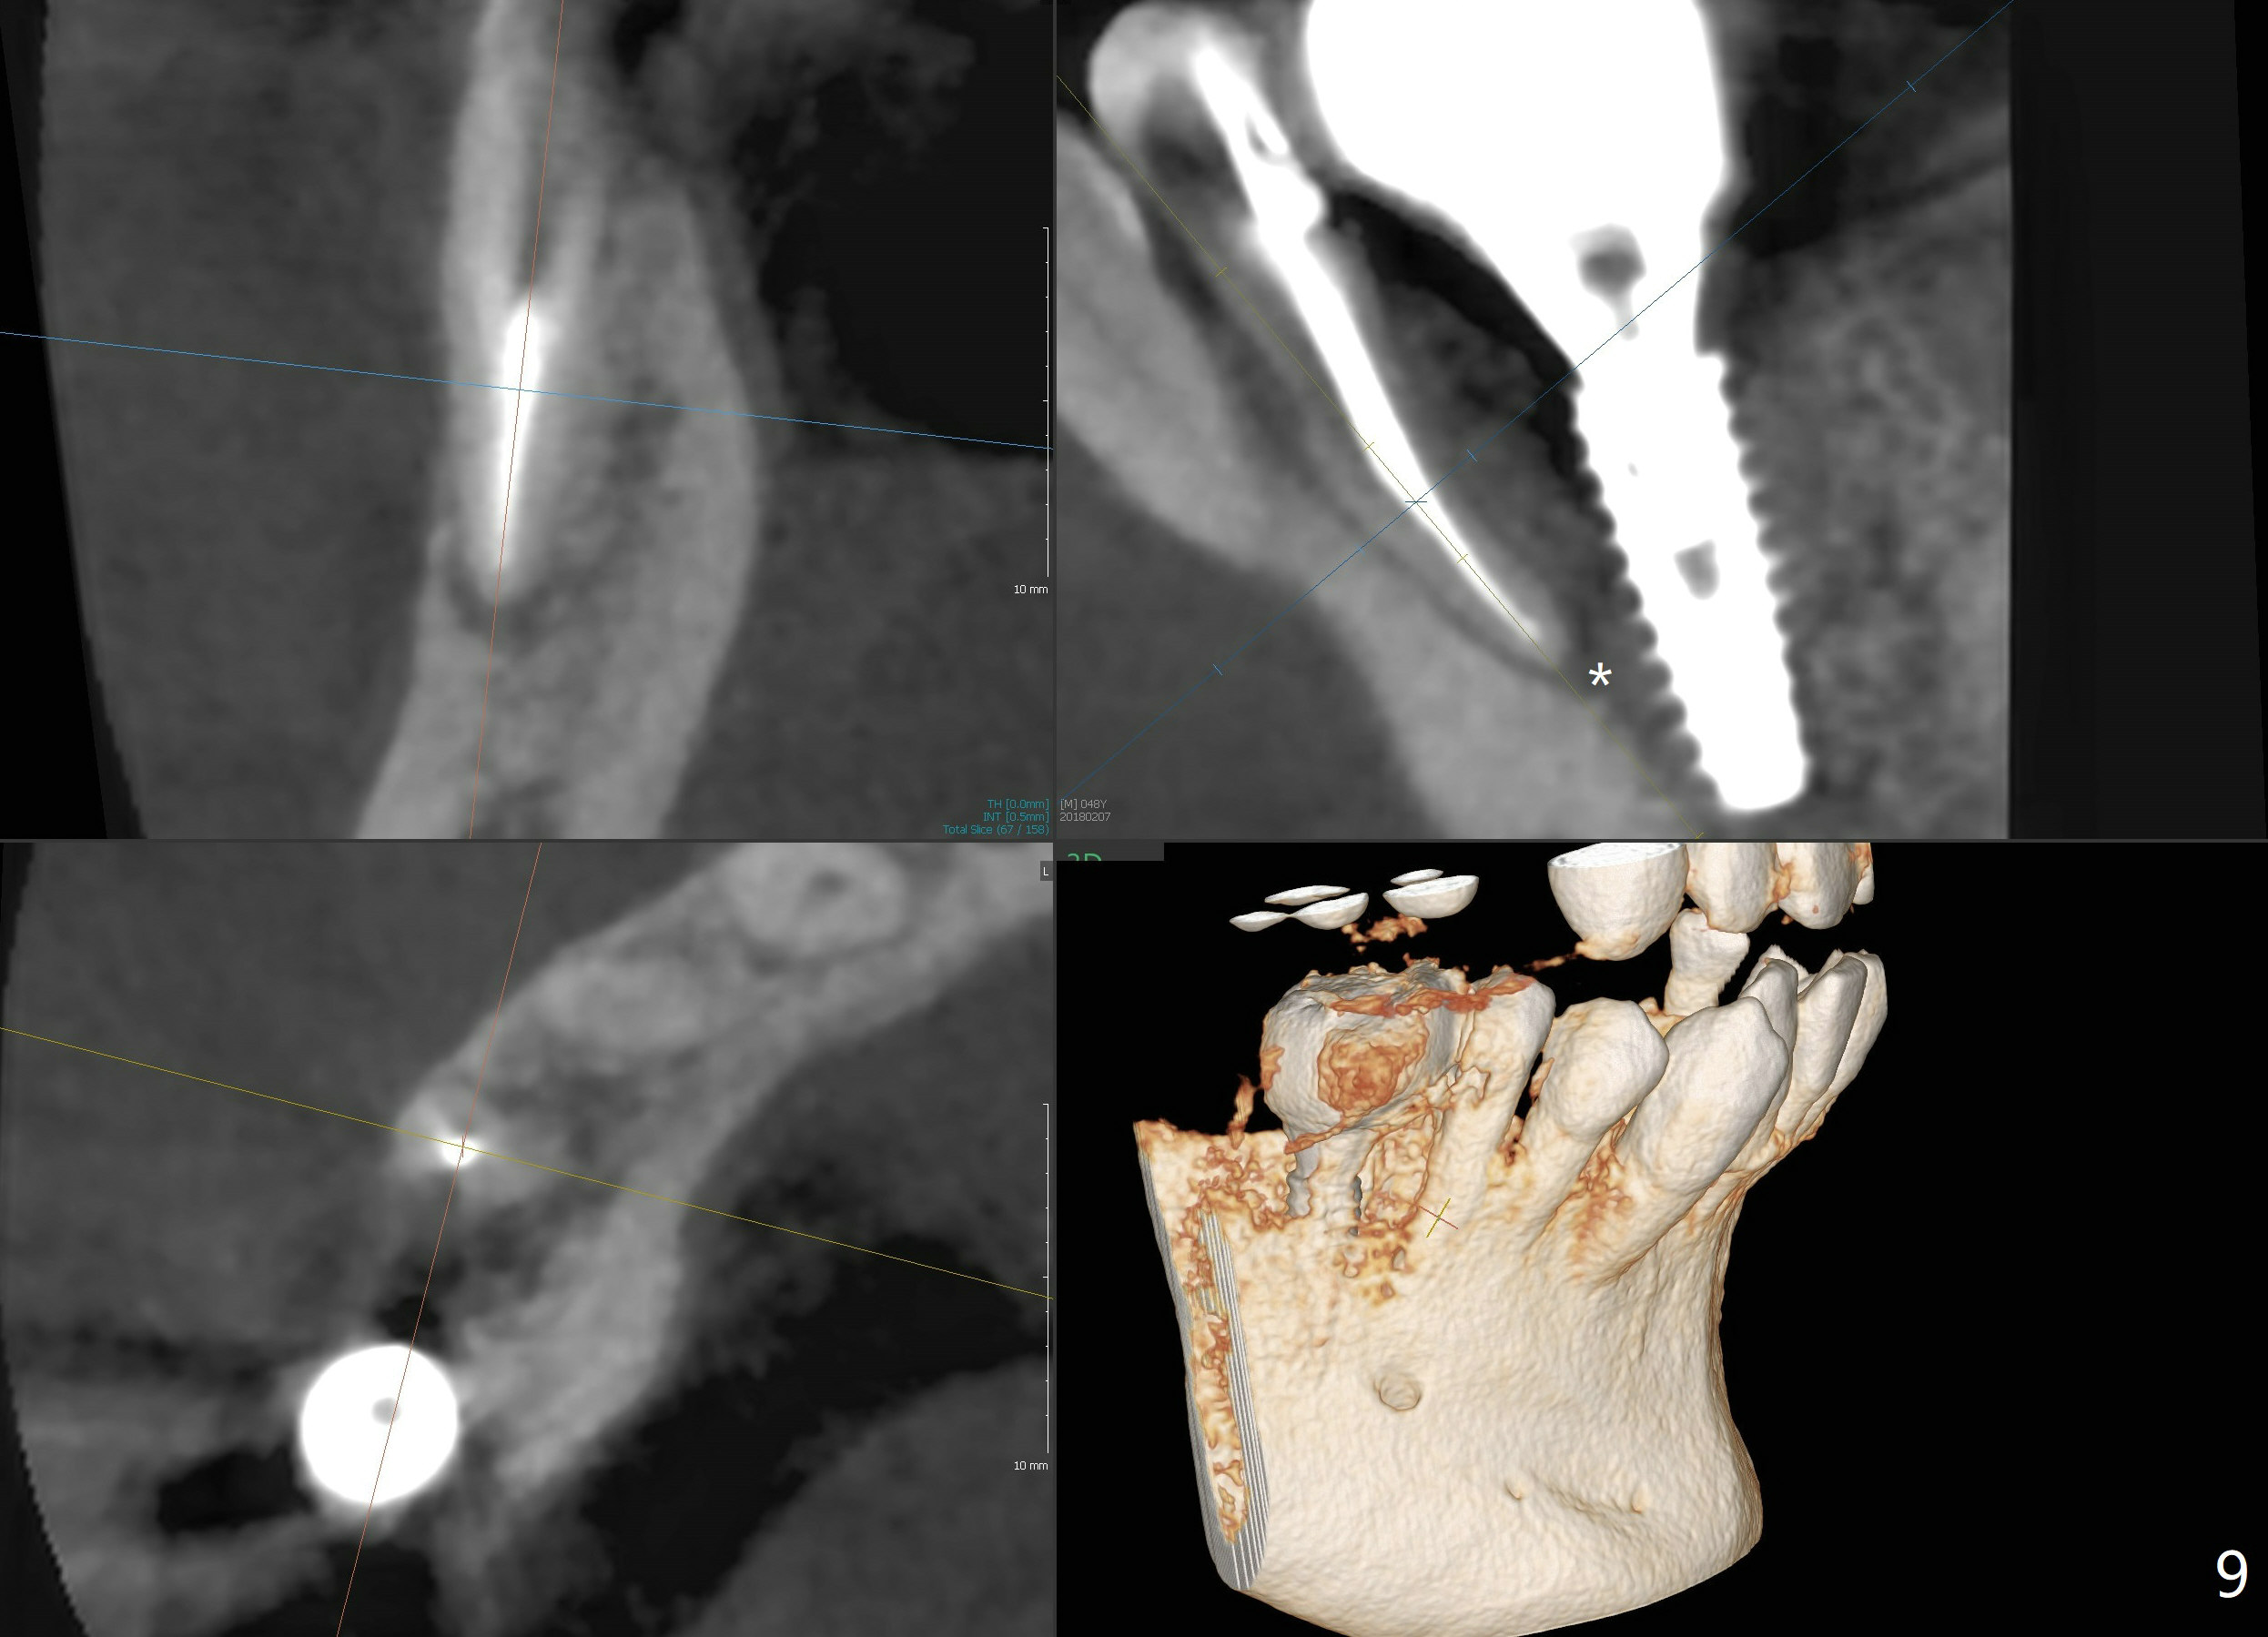

Bone graft seems to sink down and becomes denser 3 months postop (Fig.6 arrow). The bone continues being denser 5 months postop (Fig.7). There is periapical radiolucency of the tooth #29 (^). RCT is done (Fig.8). The pain persists 2 weeks postop (Fig.9,10). There is no missing canal (Fig.9). The apex is close to the implant (Fig.9 *). Apicoectomy will be performed if needed. It appears that the implant is also placed buccal (Fig.10 <) and/or the implant too large for the site. Therefore there should be a 2-3 mm buccal gap before and after implant placement. Separation and reflection of the buccal flap allows better visibility. The pain persists 1 month post RCT and 6 months post implant placement. RCT retreatment is initiated (Fig.11,12) with placement of Calcium Hydroxide paste after redebridement with 30/.04 rotary file at 23.5 mm (.5 mm longer than the earlier RCT, Fig.13). RCT retreatment finishes with apparent transportation and extrusion in 4 weeks (Fig.14,15), followed by apicoetomy (Fig.16,17) (20 days later)). Discomfort remains 2.5 months postop (Fig.18). Keep watching.